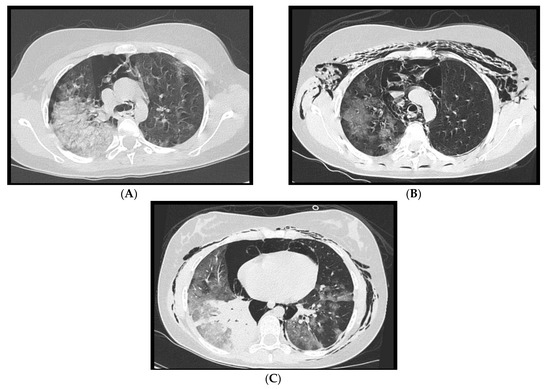

Figure 10. (AC): A 14-year-old girl with spontaneous pneumothorax and pneumomediastinum, in association with extensive ground glass changes. In Figure 10C consolidation of the right lower lobe is noted.

3.5. Pneumothorax and Pneumomediastinum

Spontaneous pneumothorax and pneumomediastinum (Figure 10) are also very infrequent findings in pediatric COVID-19-related pneumonia: a study [27] reported pneumothorax in 2% of cases, and a few case reports in the literature have described these findings [33,34], usually in adolescents with severe disease.